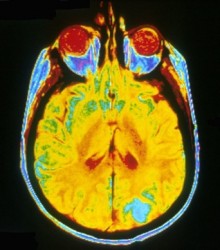

Tuberous sclerosis complex (TSC) is a relatively common genetic disorder that causes benign tumors (hamartomas) to form in many different organs, including the brain. These brain lesions can lead to seizures, autism, cognitive, and behavioral disorders. Mutations in two genes – TSC1 or TSC2 – are responsible for almost all cases.

In the January issue of Neurobiology of Disease, Kevin Ess, M.D., Ph.D., and colleagues show that mice genetically engineered to lack Tsc1 in the brain die prematurely, have increased brain size, and have various anatomical and cellular abnormalities in both neurons and glia (the supporting cells in the brain). Additionally, activity of the “mammalian target of rapamycin complex” (mTORC1 and mTORC2) pathways was altered in brain cells, and treatment with rapamycin (a drug commonly used to combat organ rejection) prevented premature death and reversed glial abnormalities. The results suggest that a postnatal treatment window may exist for combating some of the neurological and cognitive effects of TSC.